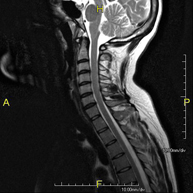

- Thoracic spine MRI

This non-invasive diagnostic procedure uses an electromagnetic field and radio waves (from a transmitter and receiver) to acquire high-definition anatomical images of the thoracic spine. It is a radiation-free procedure. Indicated for: trauma, degenerative problems, hernias, tumours.

- Lumbar spine MRI

This non-invasive diagnostic procedure uses an electromagnetic field and radio waves (from a transmitter and receiver) to acquire high-definition anatomical images of the lumbar and sacral regions. It is a radiation-free procedure. Indicated for: trauma, sciatica, herniated discs, tumours, infections.